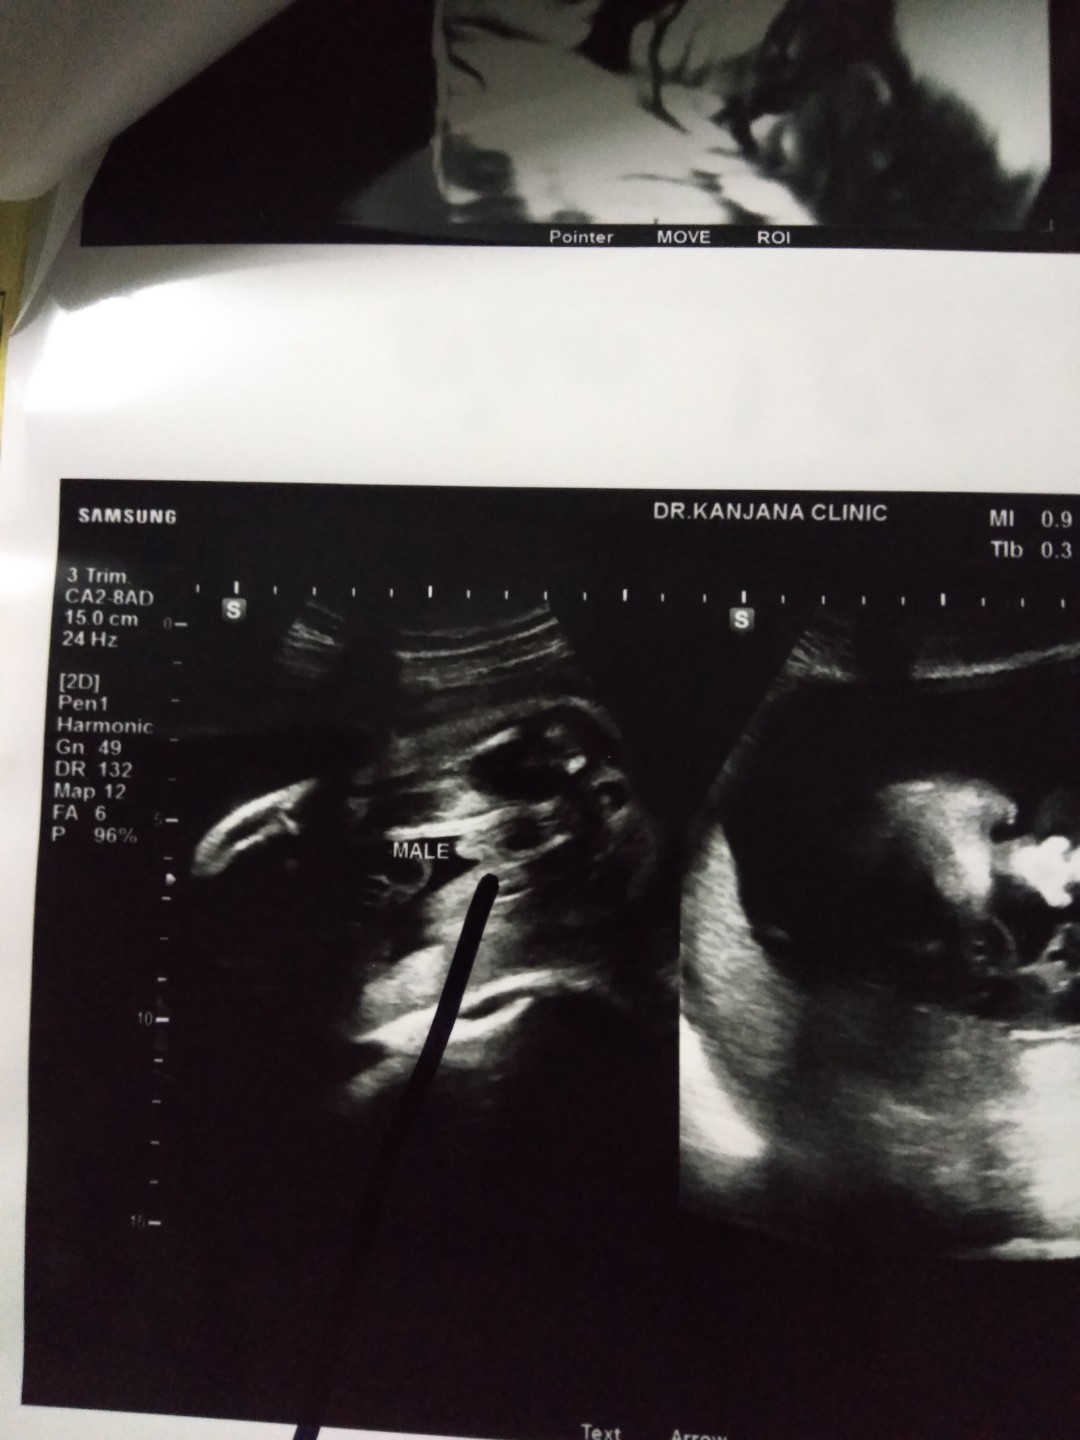

ใบอัลตร้าซาวด์

แม่ๆช่วยดูหน่อยคะ ผช.ใช่ไหมคะ หมอบอก ผช. บ้านไหนได้ ผช. ลงรูปใบซาวด์ให้ดูหน่อยคะ

ชายค่ะ

ผช. ค่ะ

ผ.ช ค่ะ

ผช. จ้า

ผช ค่ะ

ผช.จ้า

ผช.ค่ะ

ผชจ้า

ผช.คะ